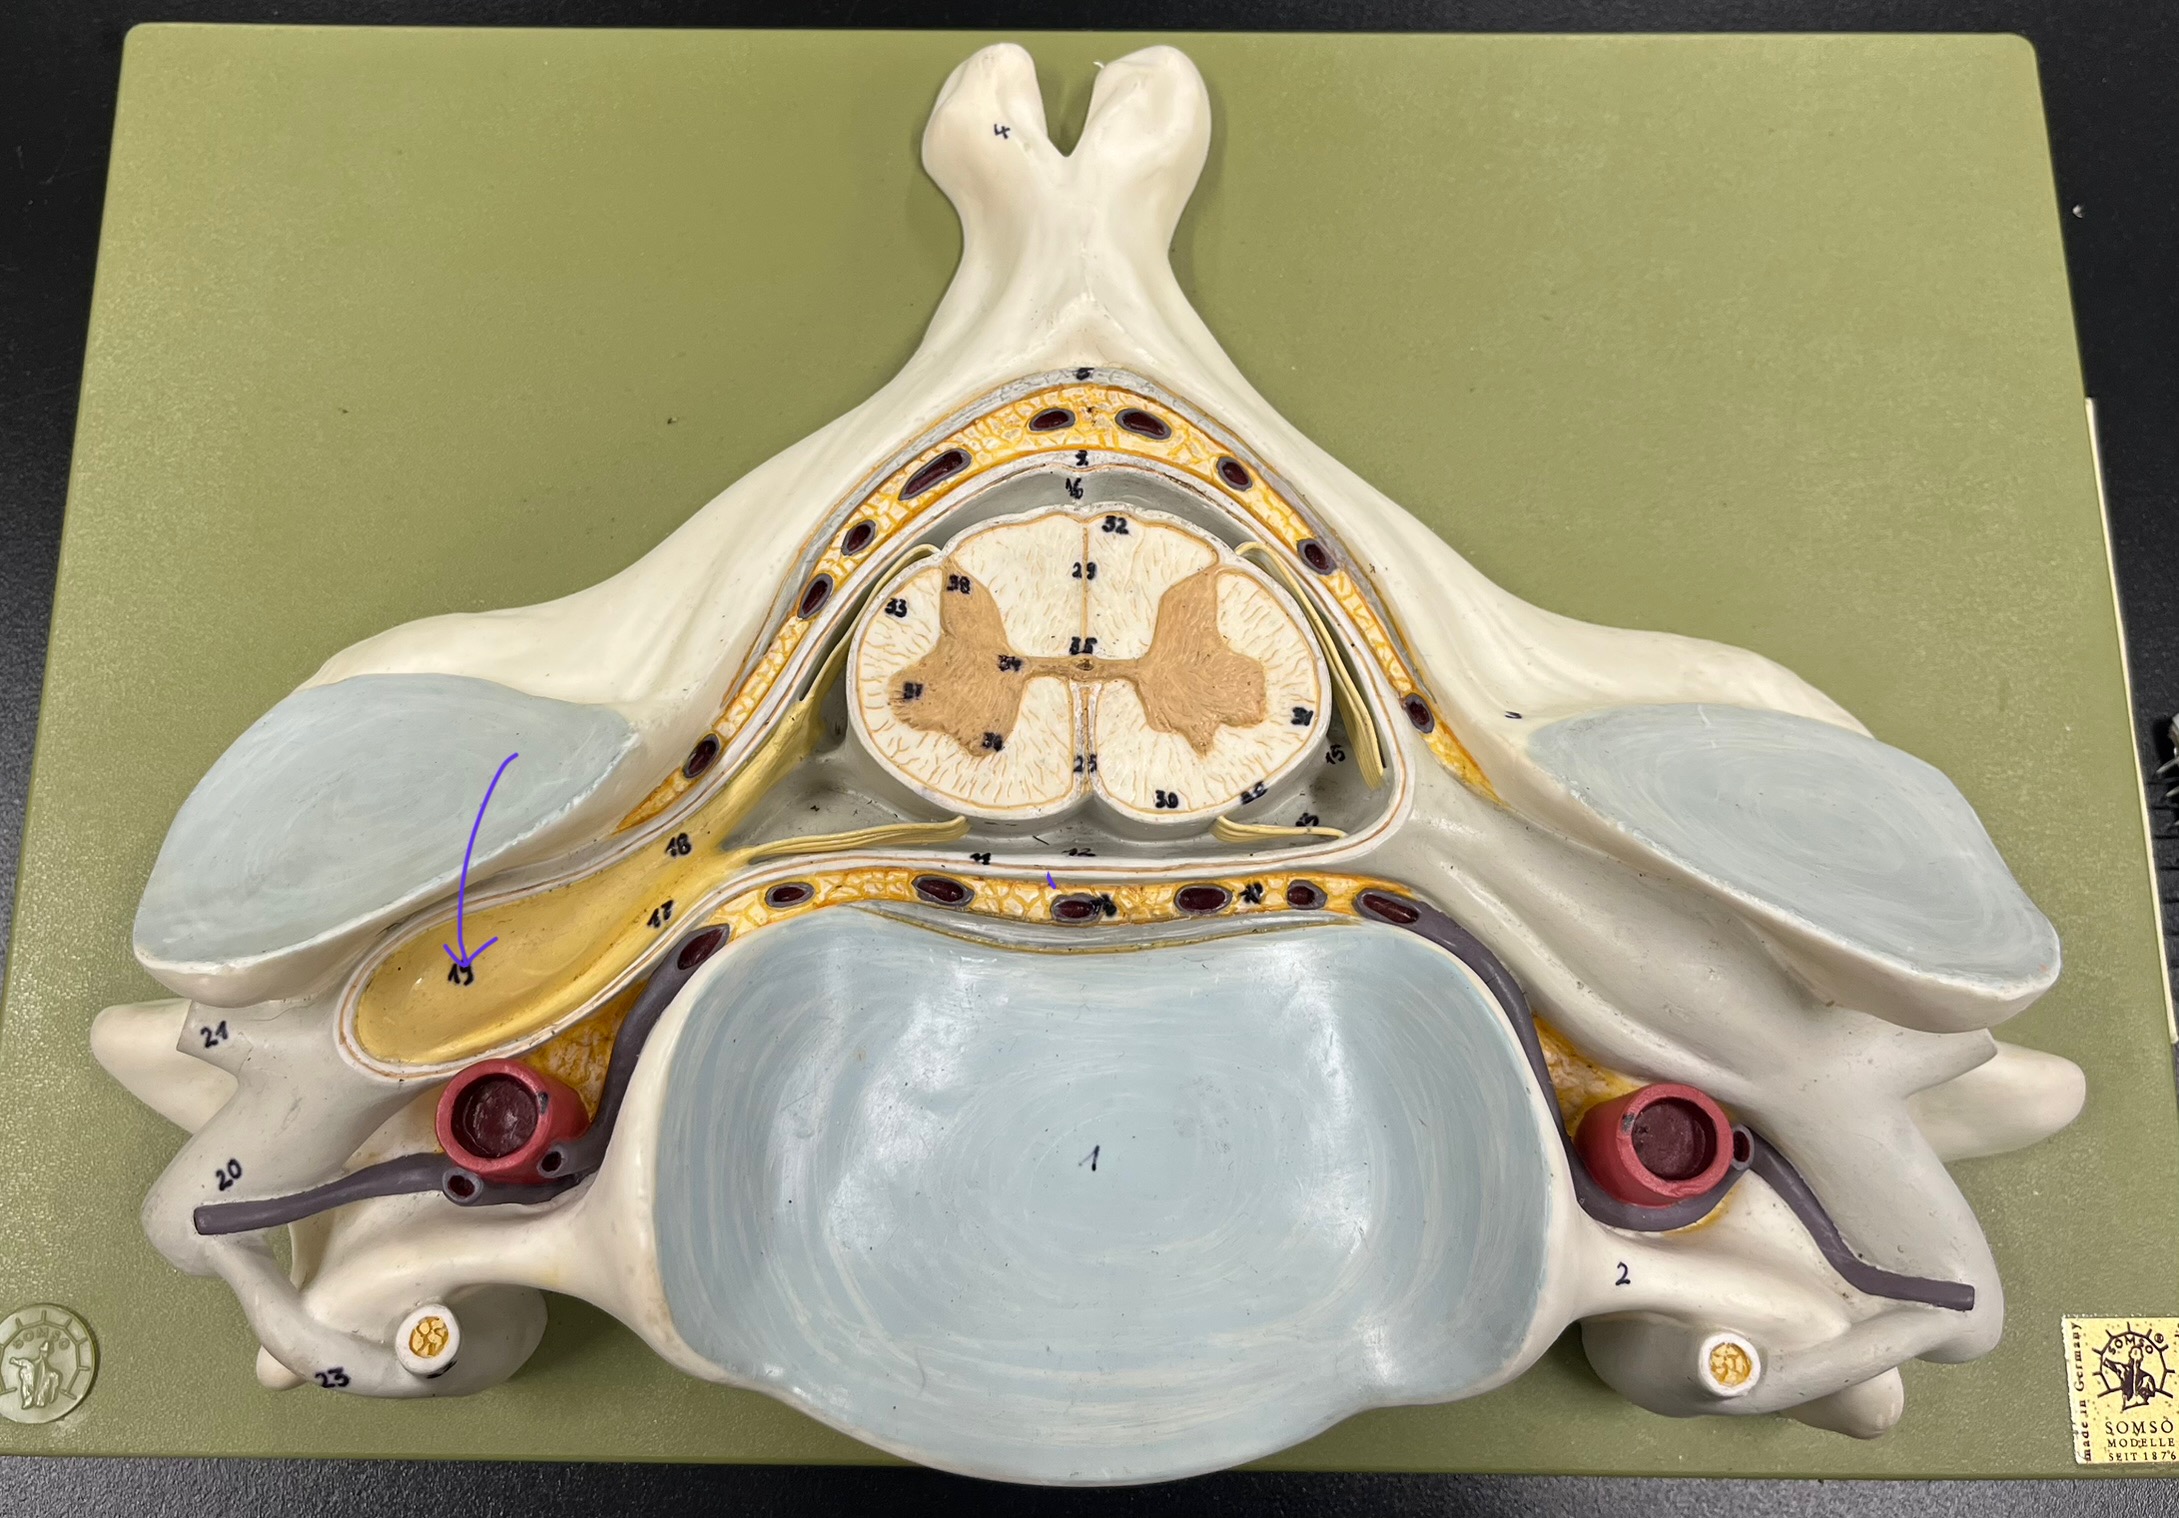

epidural space

dura mater

subdural space

arachnoid mater

subarachnoid space

pia mater

denticulate ligaments

What is the groove here?

anterior median fissure

posterior median sulcus

posterior (dorsal) horn

posterior (dorsal) horn; R—>L

anterior (ventral) horn

lateral horn (selected models)

gray commissure

central canal

anterior column

lateral column

posterior column

white commissure

posterior (dorsal) root ganglion

What is the bulb here?

posterior (dorsal) root ganglion

posterior (dorsal) root

posterior (dorsal) root

anterior (ventral) root

anterior (ventral) root

dorsal ramus

dorsal ramus

ventral ramus

ventral ramus

rami communicantes

rami communicantes

sympathetic chain ganglia

sympathetic chain ganglia